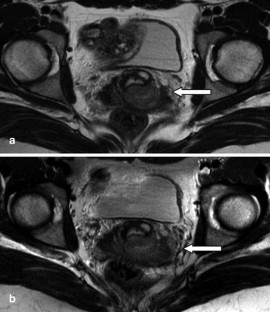

The purpose of this study was to evaluate if 3.0 T allows for clinically useful pelvic magnetic resonance imaging, i.e. if familiar image quality and tissue contrast can be achieved at 3.0 T as compared with at 1.5 T. Adapting a 1.5-T protocol to the 3.0-T environment is subject to a variety of factors. In order to reduce the number of potential variables, we chose two cornerstones: the 3.0-T sequence should have similar spatial resolution and acquisition time; furthermore, the contrast parameters repetition time (TR) and echo time (TE) were kept identical. Based on this modified 3.0-T T2-weighted turbo spin-echo sequence (TR/TE 2,705/80 ms; 0.7×1.04×4 mm measured voxel size; field of view 360 mm; 4.03-min scan time) we performed an intraindividual study on 19 patients with the 1.5-T sequence as the standard of reference. Two radiologists analyzed the examinations in consensus with regard to tissue contrast (visualization of zonal anatomy of the uterus and/or delineation of pathologic findings) rated on a three-point scale (3 is 3.0 T better; 2 is 3.0 T equal; 1 is 3.0 T worse than 1.5 T). In addition, the signal difference between muscle and bone marrow was measured as a marker for tissue contrast. The analysis of the image quality comprised the level of the artifacts (rated on a five-point scale: 1 is no artifacts; 5 is nondiagnostic study), the visual signal-to-noise ratio (rated on a three-point scale) and detail delineation. Only minor artifacts were observed at both 1.5 and 3.0 T; the difference was not statistically significant. The visual signal-to-noise ratio and the delineation of image details were rated equal for 1.5 and 3.0 T. With regard to image contrast, both qualitative analysis as well as quantitative analysis revealed comparable image contrast for the 1.5- and 3.0-T protocols. Pathological findings were seen equally well with both field strengths. Clinically diagnostic pelvic studies of high image quality can be obtained using a 3.0-T scanner with our modified examination protocol. To fully exploit the capability of the high-field technique, and to point out potential advantages, further intraindividual studies are needed, with the adjustment of other imaging parameters to the high-field environment.

Fig. 1